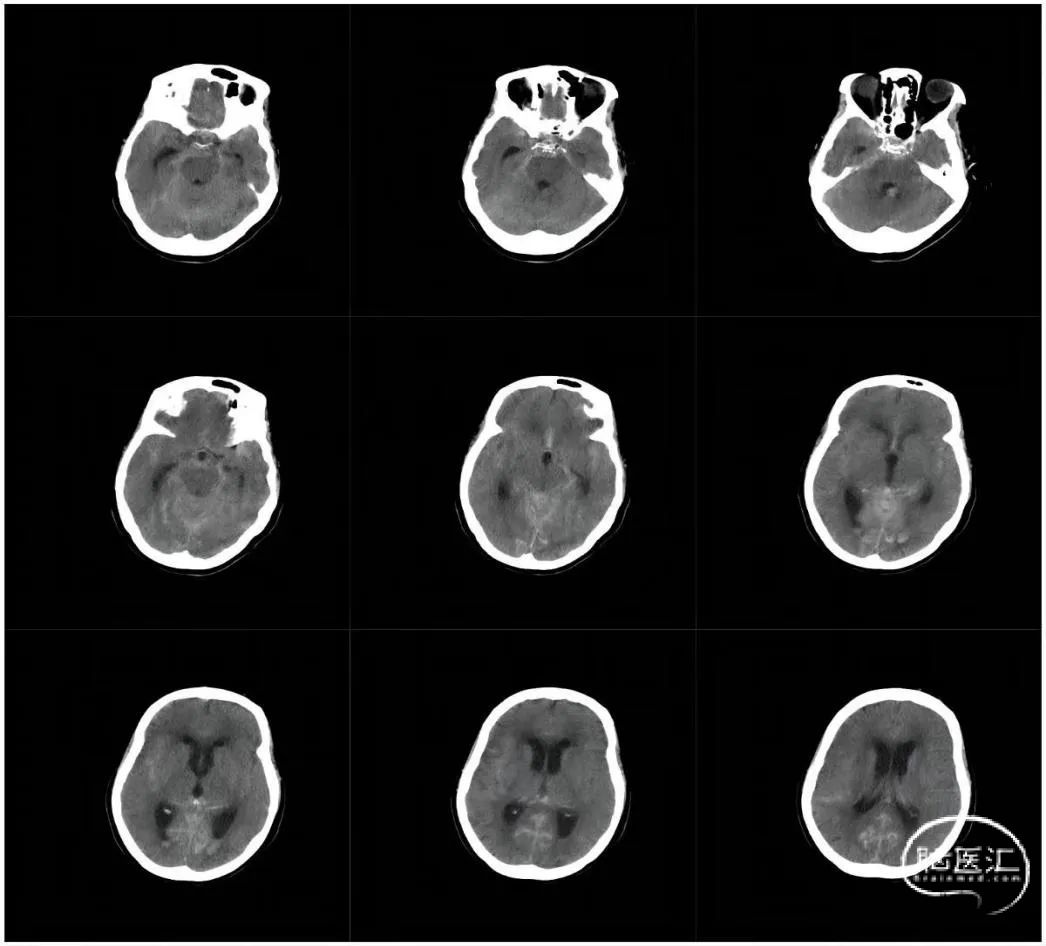

术前影像

CT平扫